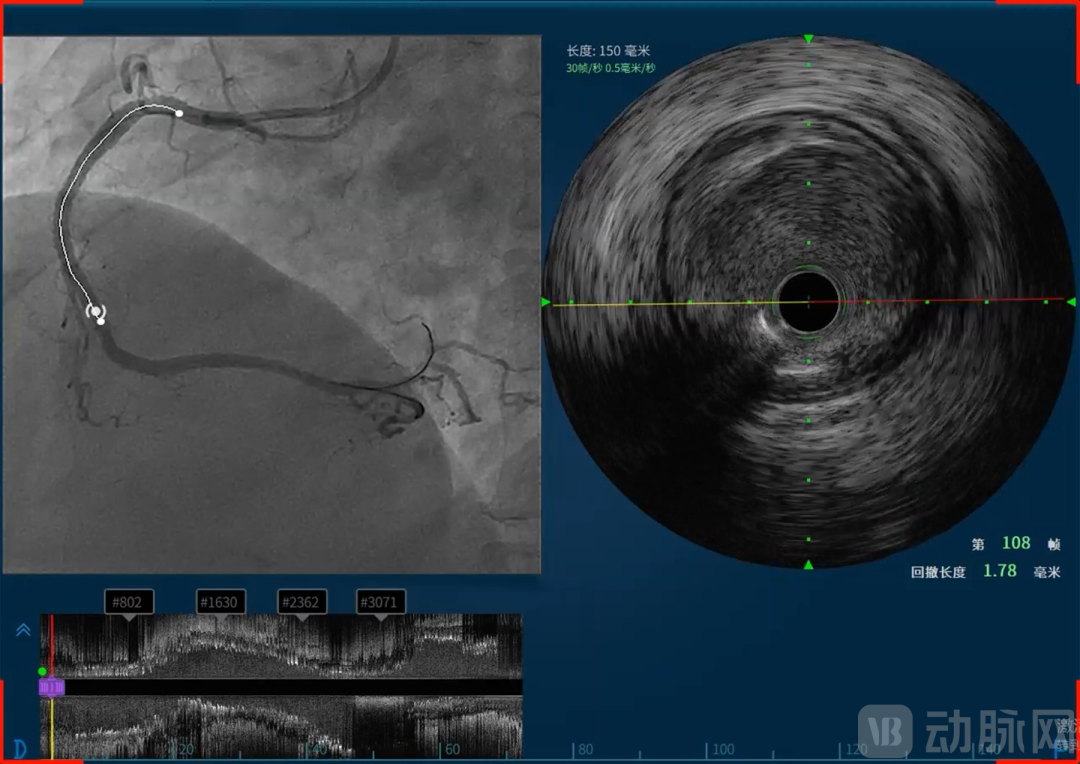

恒宇医疗的吸引力不仅在于所深耕的血管介入赛道,更在于其致力于构建的完整技术体系和难以复制的研发能力。恒宇医疗深耕血管内超声(IVUS)和光学相干断层成像(OCT)技术领域多年,形成了从核心元器件到整机设备,从单一产品到系统解决方案的全链条布局。恒宇医疗是国内少数同时掌握IVUS和OCT两项核心技术的企业,这种“双技术路线”并行的能力使其在血管介入精准诊疗领域占据了独特位置。同时融合OCT与近红外光谱(Near-Infrared Spectroscopy, NIRS)的单光源双模态OCT-NIRS技术的成功,更使恒宇医疗成功建立了OCT/IVUS/NIRS三模态成像模式,为临床诊疗提供了更为全面的解决方案。

天津恒宇医疗成立于2016年,专注于血管内超声(Intravascular Ultrasound, IVUS)设备及导管、光学相干断层成像(Optical Coherence Tomography, OCT)设备及导管、IVUS/OCT一体机式的双导管系统、基于IVUS和OCT的无创血流储备分数(Fractional Flow Reserve, FFR)平台、融合OCT与近红外光谱(Near-Infrared Spectroscopy, NIRS)的单光源双模态OCT-NIRS技术及血管内激光斑块消蚀技术的自主研发、生产和销售,掌握光学、超声及导管平台技术,并不断基于底层技术进行全球领先的创新,致力于为医患提供以影像类产品为基础的泛血管一体化解决方案。